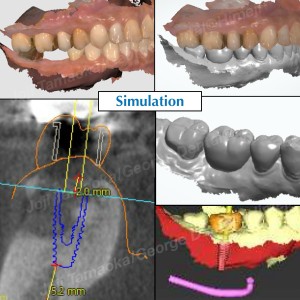

▶︎ 3ヶ月後:骨の回復がとても良好

術後3ヶ月のCTでは、非常に良好な骨の再生が確認できました。

通常、骨が不足すると「骨造成(GBR)」が必要になりますが、今回は

ソケットプリザベーションのおかげで追加の外科処置は不要。

そのままシンプルにインプラント埋入が可能となりました。

▶︎ デジタル技術による安全なインプラント手術

今回もガイドを用いることで、短時間で正確な埋入が実現しました。